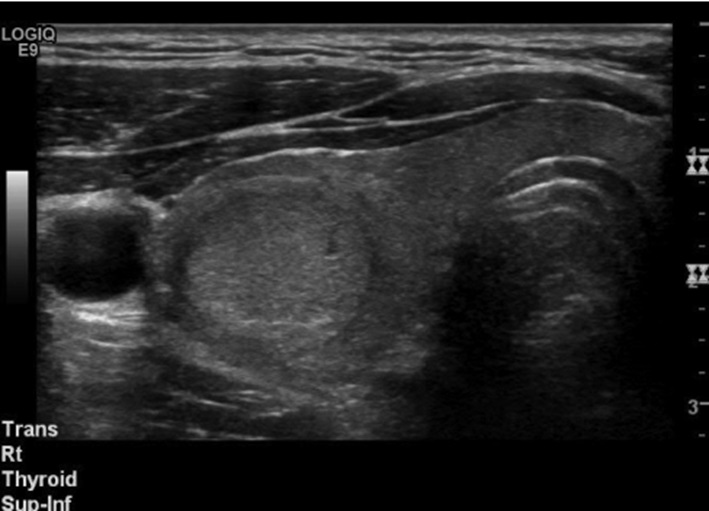

Hình ảnh siêu âm của u lành tuyến giáp

Siêu âm tuyến giáp là phương pháp hình ảnh quan trọng nhất, cho phép phân loại u dựa trên đặc điểm hình thái. Các yếu tố như độ hồi âm, bờ, vi vôi hóa, hình dạng và mạch máu nội khối giúp phân biệt giữa u có nguy cơ ác tính và u lành tính. Nhiều hiệp hội, trong đó có ATA và ETA, đã đưa ra các hệ thống phân loại nguy cơ dựa trên siêu âm như TIRADS (Thyroid Imaging Reporting and Data System). Các hệ thống này giúp bác sĩ lâm sàng xác định trường hợp nào cần FNA và trường hợp nào chỉ cần theo dõi.